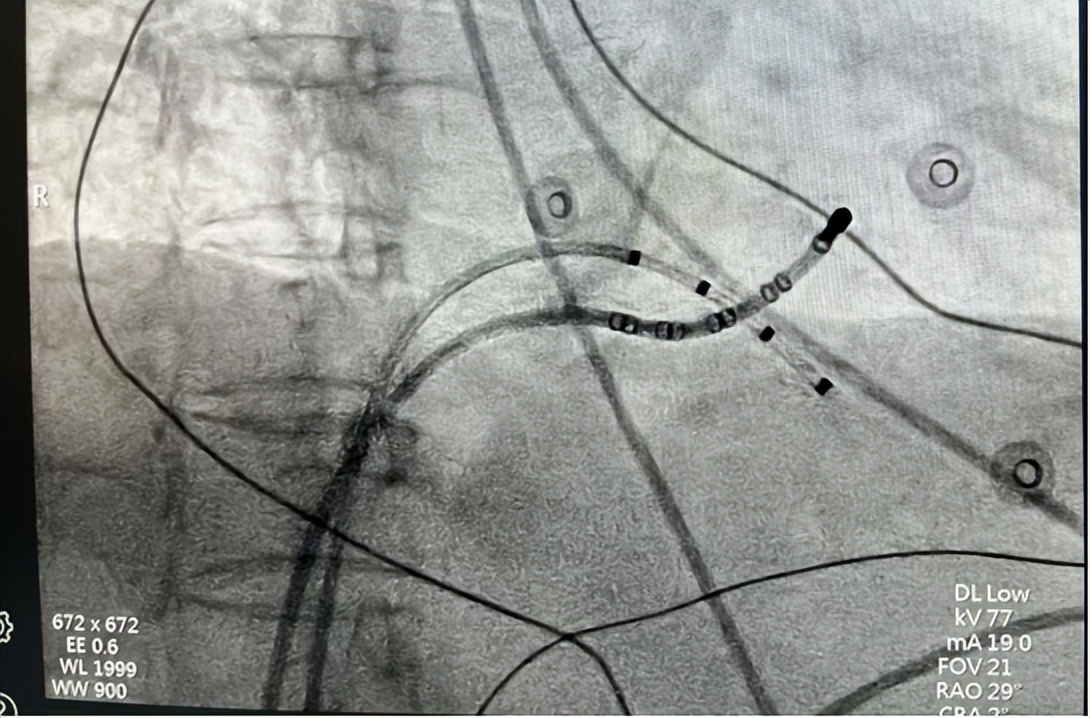

△术中导管放置

△导管图